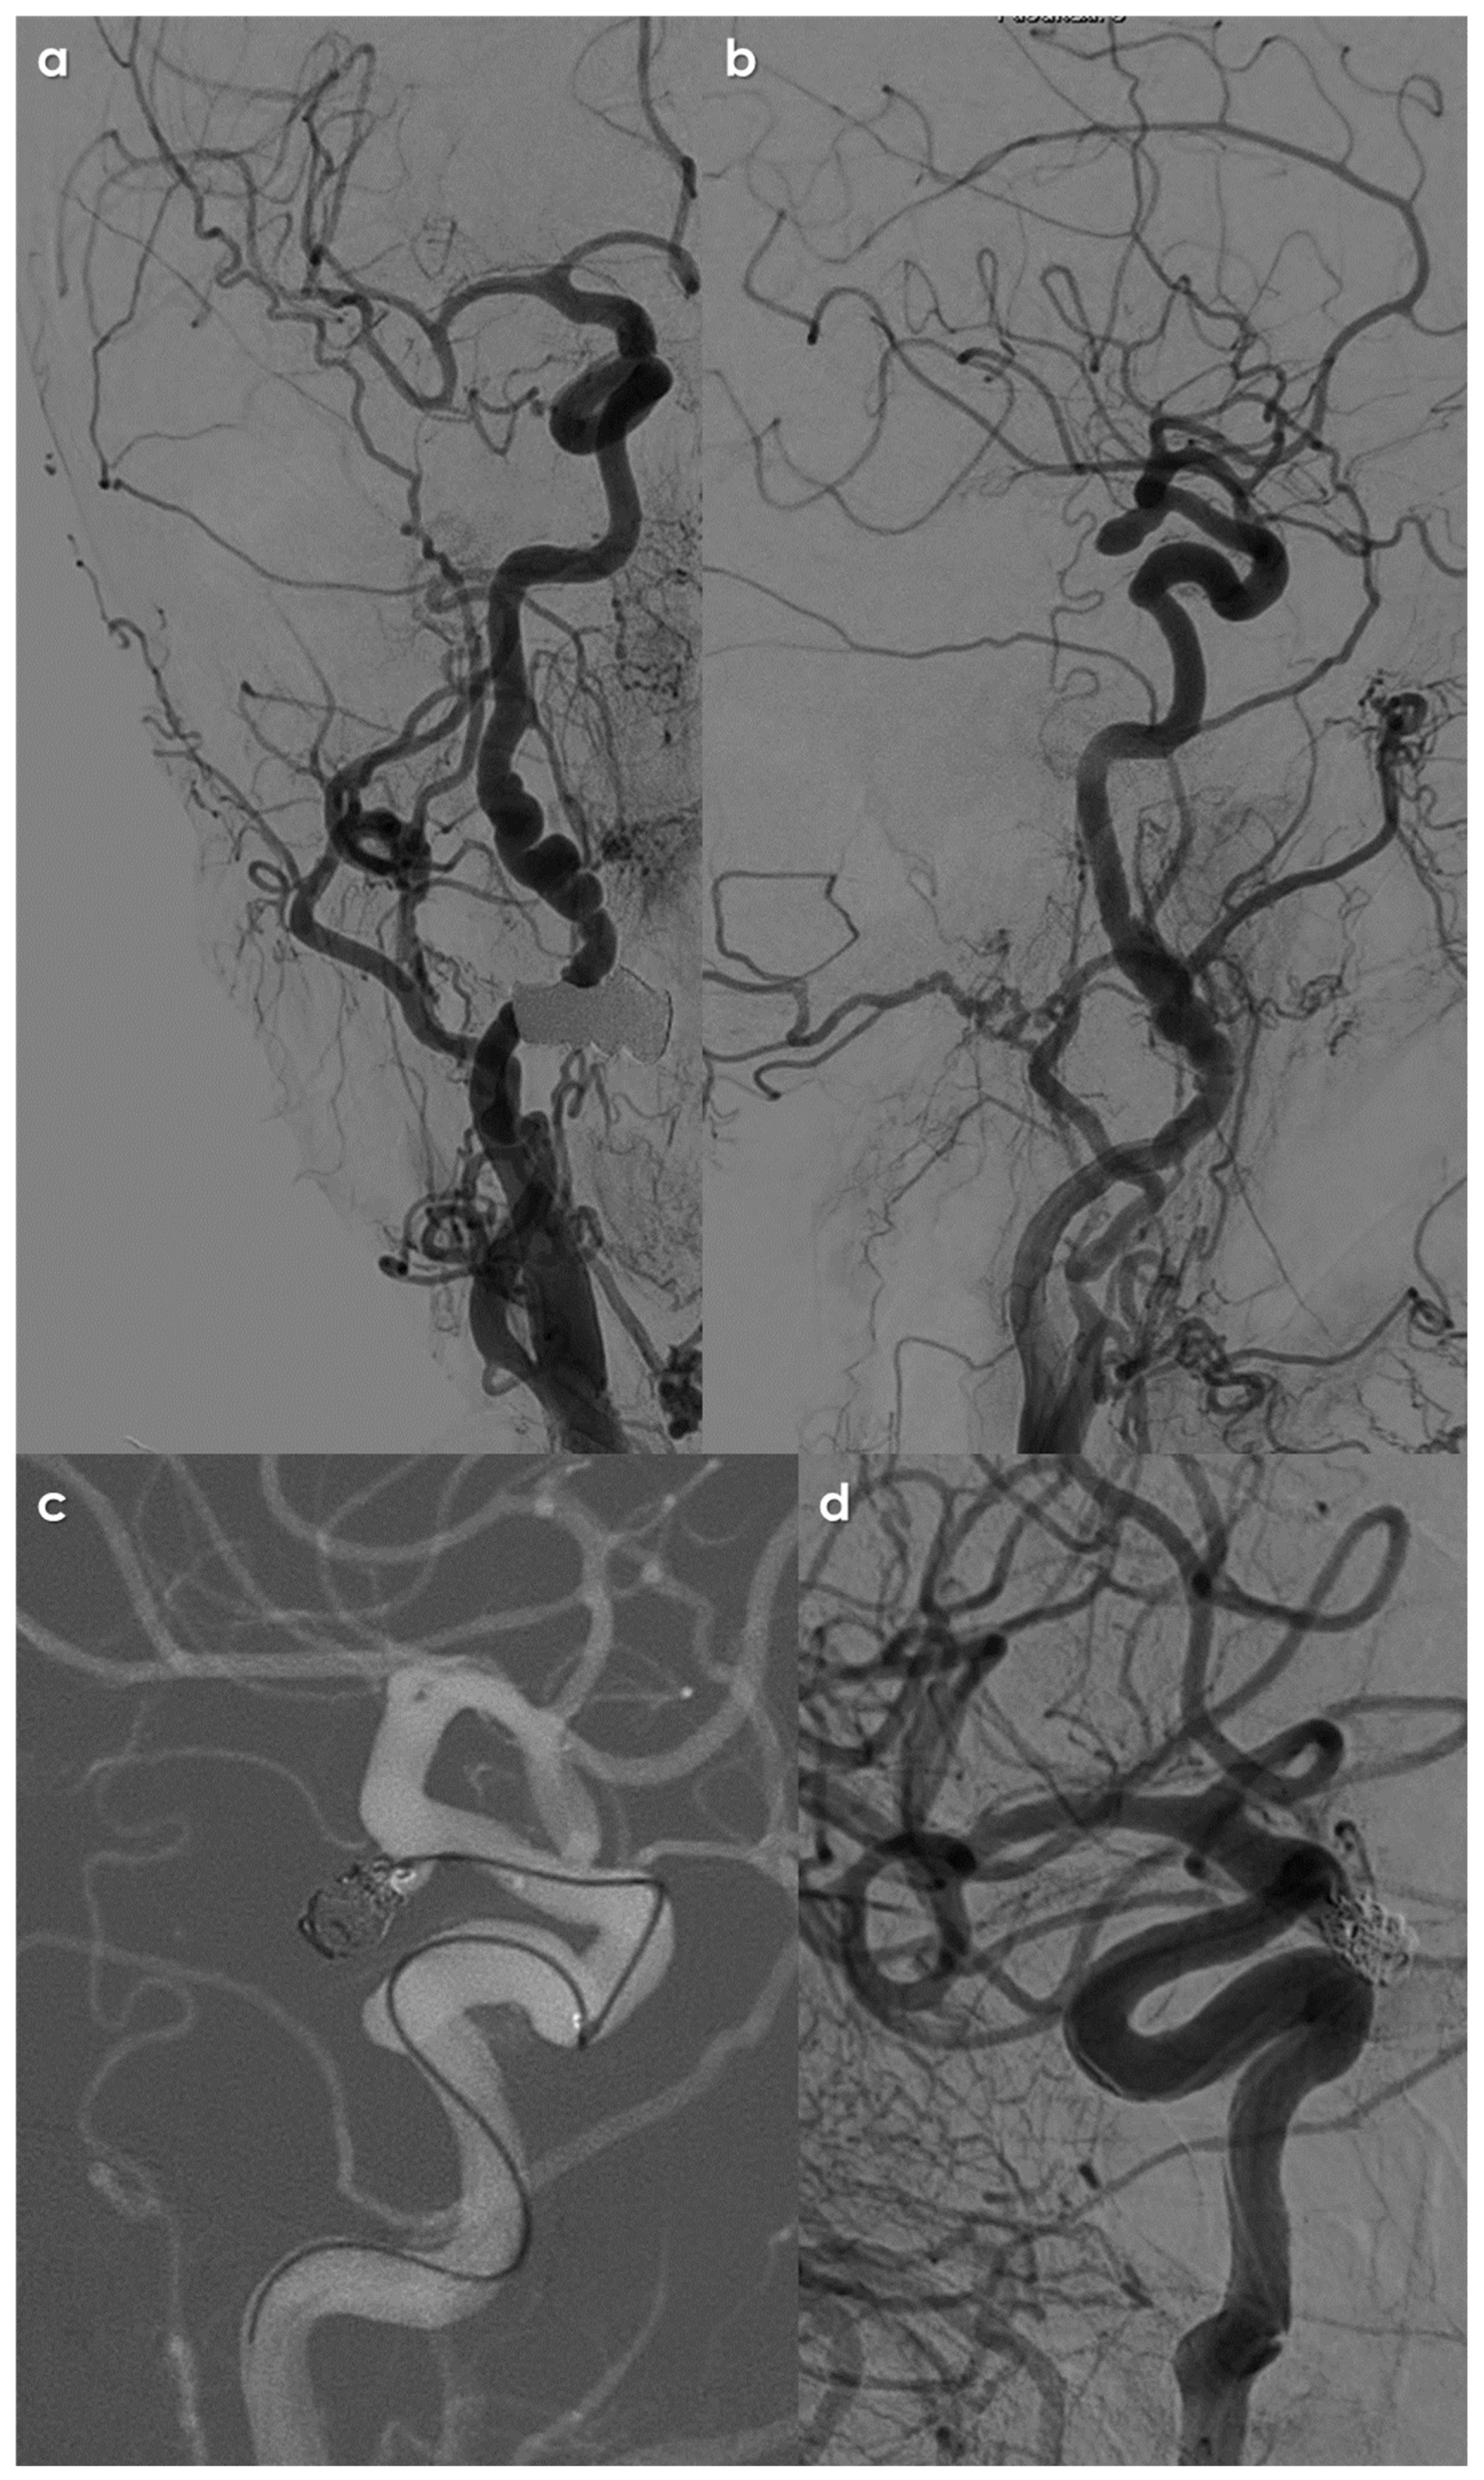

2. Materials and Methods

3. Results

3.3. Features of Intracranial Aneurysms

- Size of Aneurysms: 56/128 (43.2%) aneurysms were ≥5 mm, i.e., at high risk of rupture, illustrating a higher risk profile compared to general population findings. The sizes were categorized as in Figure 1.

- Location of Aneurysms: The distribution of IAs was notable, with a significant number located in areas typically associated with higher risks of rupture. A substantial 41% of the identified intracranial aneurysms were located in the intradural segments of the ICA, which is considered a high-risk area, along with 12% in the posterior communicating artery and 9% in posterior circulation arteries.

- Multiplicity: Many patients presented with multiple IAs, indicating a possible underlying susceptibility linked to the pathophysiology of FMD. The median number of aneurysms per patient was 1, but some had as many as 8 intracranial aneurysms.

3.4. Treatment Issues